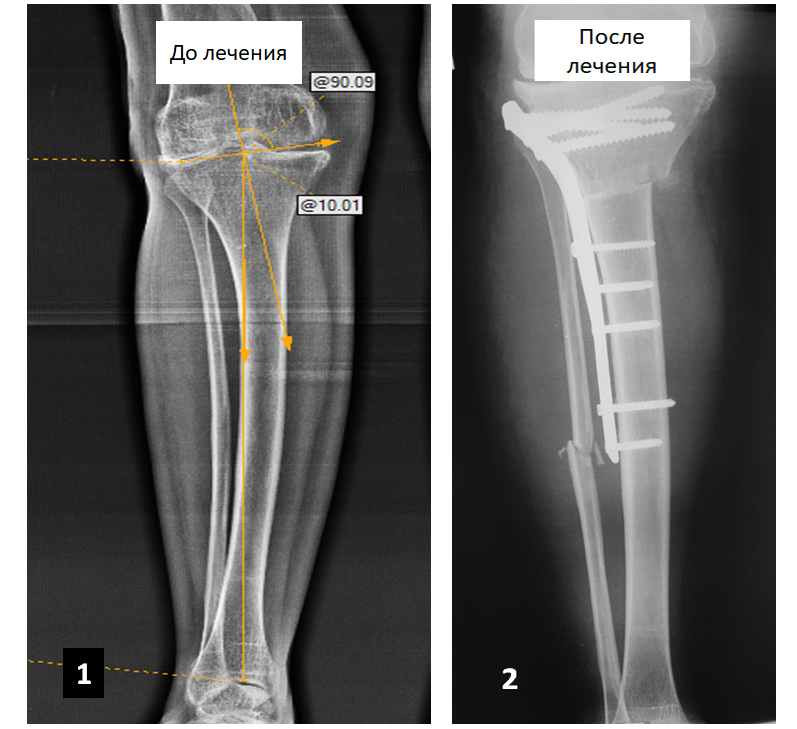

Чоловік звернувся за допомогою зі скаргами на болі в області лівої гомілки та лівого колінного суглоба. Під час консультацій в інших медичних установах пацієнту було запропоновано виконати протезування лівого колінного суглоба, від якого він відмовився.

Після проведення обстежень була виявлена ​​установча варусна деформація лівої гомілки і виконана коригуюча резекція лівої великогомілкової кістки, в результаті якої вісь кістки була відновлена.

В даний час болі пацієнта не турбують, він повноцінно користується кінцівкою протягом трьох років після операції.